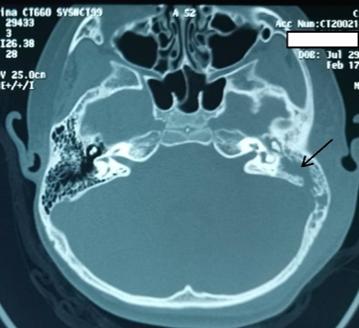

拿出CT一看,好厉害!只见左侧中耳和乳突内软组织填充,乳突气房已融合成大腔,外侧软组织肿胀。同侧颅后窝乙状窦表面骨质可疑缺损。这是典型的急性中耳炎的颅外并发症——耳后骨膜下脓肿。